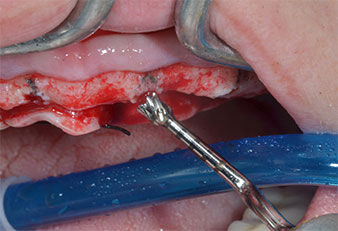

Implant motor (Implantmed)

Fig. 5: The final diameter is achieved with the Piezomed I3A/I3P instruments. For the 10-mm implants at positions 11 and 21 sites are finalized with a 3.5 mm rotary drill in an implant motor (Implantmed).

In case of dense bone the whole instrument sequence including the intermediate instruments Piezomed Z25P and Z35P should be used to widen the osteotomies before the next enlargement step.

They are also indicated for preparation near the sinus membrane in connection with internal augmentation procedures or when there is less than 4 mm of residual bone height.

In the present case the Z25P and Z35P instruments were not used due to the relatively soft posterior bone, which was easily managed with the I3A/I3P.

Due to the relatively hard bone (D2) in this area, the 10 mm long implant sites at positions 11 and 21 were finalized with a 4 mm diameter rotary drill, in combination with a W&H WS-75 L surgical contra-angle handpiece, the W&H Implantmed implant motor and the optional W&H Osstell ISQ module. In contrast, due to the soft bone the posterior sites were prepared to a final 3 mm diameter using the Piezomed I3P instrument. The implants were finally placed transgingivally to osseointegrate for three months (Figs. 6-10). The existing denture was retained on four provisional implants (Fig. 8).